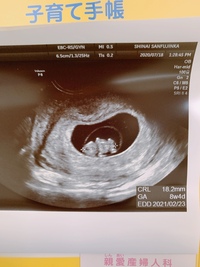

赤ちゃん241mmです。 1人目は成長遅くこの時期でやっと心拍確認出来たくらいなので、今回は順調でホッとしています( ¨̮ ) 胎嚢の下に大きめの血腫があり自宅安静中ですが、負けずに大きく育てー!!楽天市場手芸の山久の手編み > キット・セット > 赤ちゃん・子供用一覧。楽天市場は、セール商品や送料無料商品など取扱商品数が日本最大級のインターネット通販サイトAug 15, 19 · エコーで見る赤ちゃんは217mmとごくごく順調に育っています。 胎嚢も育ってはいるのですが、やはりネットで出てくる9wのエコーと比較してしまうと、まぁ赤ちゃんが窮屈そうで。

妊娠9週1日 9w1d の超音波 エコー 写真

9w1d エコー写真 9週なのに10週のサイズ ゆるふわ 35歳マイペース不妊治療 出産